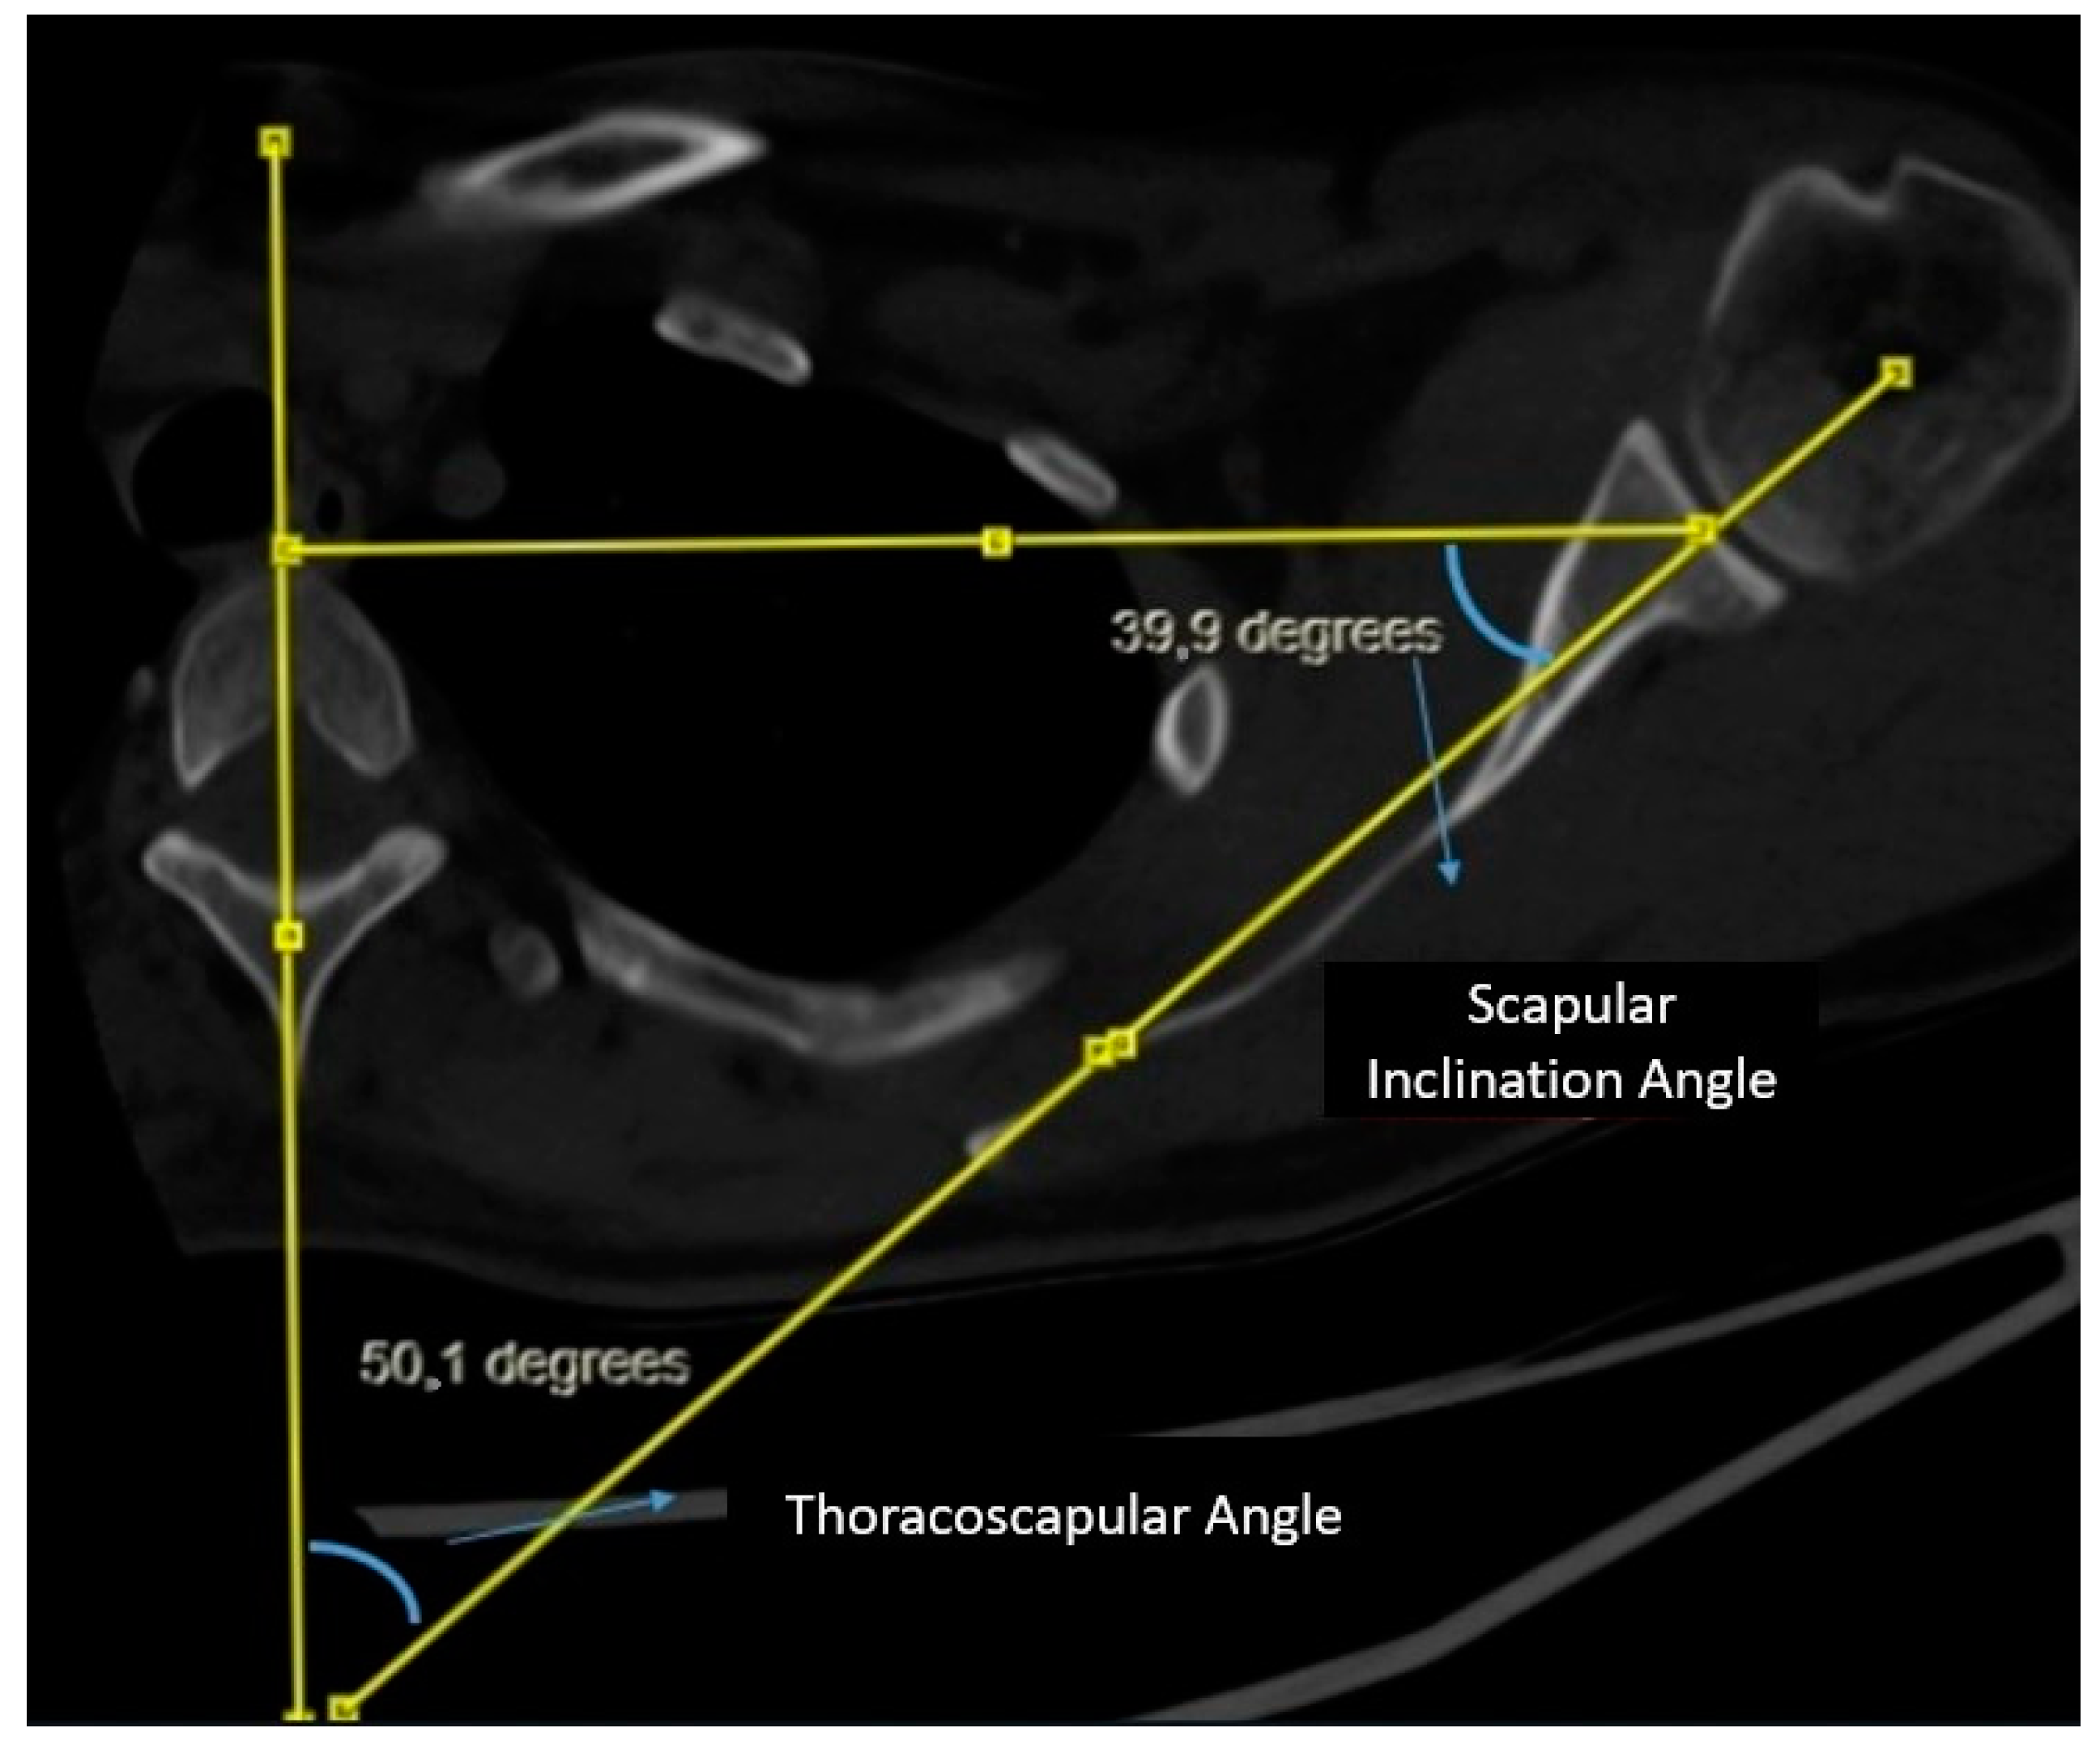

Measurement of Scapular Inclination Angle and Thoracoscapular Angle: A vertical line is drawn from the midline of the corpus and spinous process of the thoracic vertebra at the level of the spine of the scapula. Subsequently, a second line connecting the center of the glenoid to the spine of the scapula is drawn, intersecting the line through the midline of the thoracic vertebra. A triangle is formed by drawing a line from the center of the glenoid perpendicular to the vertical line on the vertebra. The angle between the line connecting the center of the glenoid to the spine of the scapula and the line drawn perpendicular from the center of the glenoid to the vertical line on the vertebra is evaluated as the scapular inclination angle. The angle between the line connecting the center of the glenoid to the spine of the scapula and the vertical line on the midline of the vertebra is evaluated as the thoracoscapular angle. It is noteworthy that the scapular inclination angle and thoracoscapular angle together complement each other to form a total of 90 degrees (Figure 2).

Figure 2. Measurement of scapular inclination and thoracoscapular angle.